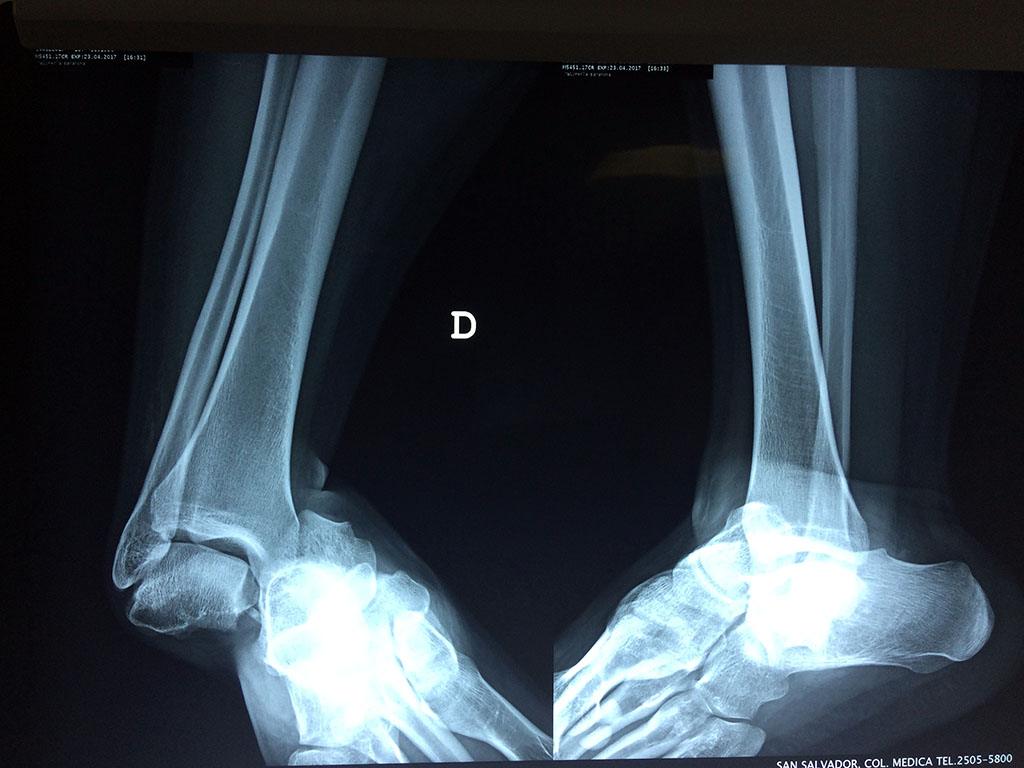

Una fractura de tobillo es la rotura de uno o más de los huesos del tobillo. Estas fracturas pueden ser:

- Completas (el hueso está perforado y está en 2 partes).

- Producirse en uno o ambos lados del tobillo.

- Los extremos de los huesos están desalineados entre sí (desplazados).

- La fractura se extiende hasta la articulación del tobillo (fractura intra-articular).